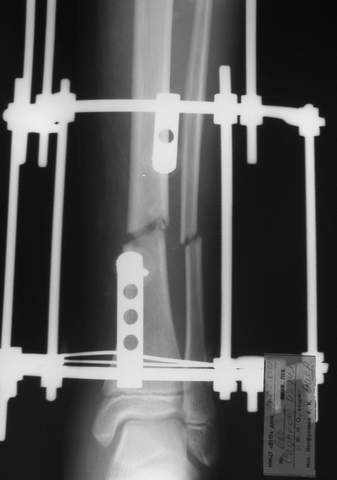

Под рукой прилагаемый пример. Как видите, "стриптиз-аппарат" (шутка проф. З.К.Башурова): 3 кольца-2 кольца-2 полукольца. В случае, который представил Евгений, характер повреждения позволил бы сразу использовать аппарат на основе 2 колец; в крайнем случае прокс. опора м.б. демонтирована сразу после репозиции.

МТ мы используем, конечно, не только на голени. В прилагаемом примере у парня при поступлении была наружная ротация 40 гр. и "полумертвый" коленный сустав. Можно был бы, конечно, до конца использовать полную компоновку. Но для того он и есть метод выбора.